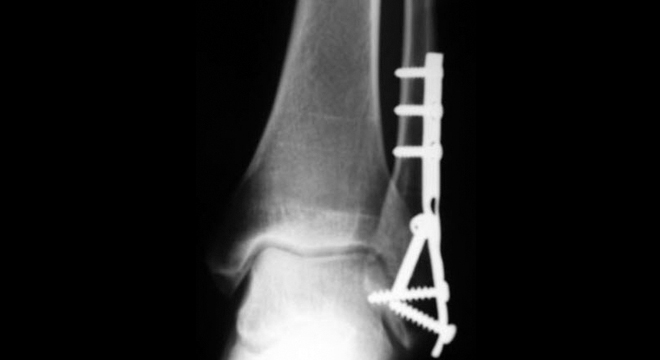

Knöchelbruch: operative Fixation und Stabilisation

Brüche, bei welchen die Syndesmose gerissen ist oder eine Instabilität des Gelenkes vorliegt, müssen operiert werden. Mit Schrauben, Platten und Drähten werden die Knochenfragmente möglichst präzis wieder in ihre Originalstellung gebracht und fixiert. Das Band wird genäht. Nach der Operation muss das Bein zuerst meist im Gips zumindest teilweise ruhiggestellt werden. Nach ca. 6-8 Wochen kann wieder normal belastet werden; die Dauer ist allerdings abhängig von der Art der Fraktur sowie der operativen Versorgung. Zur Reduktion des Thromboserisikos muss der Betroffene möglichst bald aufstehen; eine Stockentlastung ist unumgänglich.